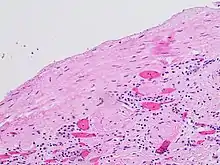

Histopathology of the lining of a simple cyst of the kidney, incidentally found on autopsy, with inconspicuous nuclei. They usually have a single layer of cuboidal, flattened or atrophic epithelium,[13] but this case has a somewhat thicker fibrous layer. H&E stain.